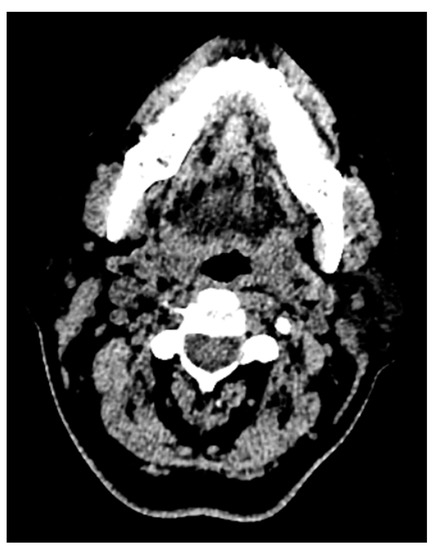

One more case of a photon starvation artifact hindering the assessment of the tongue pathology and its extent in a computed tomography image is presented in Figure 6.

This photon starvation, or quantum mottle, greatly hindered the diagnostic quality of the image. This results from insufficient X-ray photons reaching the sensor from the patient. Even though techniques such as tube current modulation (TCM) and vendor-specific and iterative reconstruction algorithms can reduce this effect, these types of artifacts still represent considerable hindrances to diagnosis and assessment.

Figure 6. Photon starvation artifact hindering the assessment of the tongue pathology and its extent in a computed tomography image.